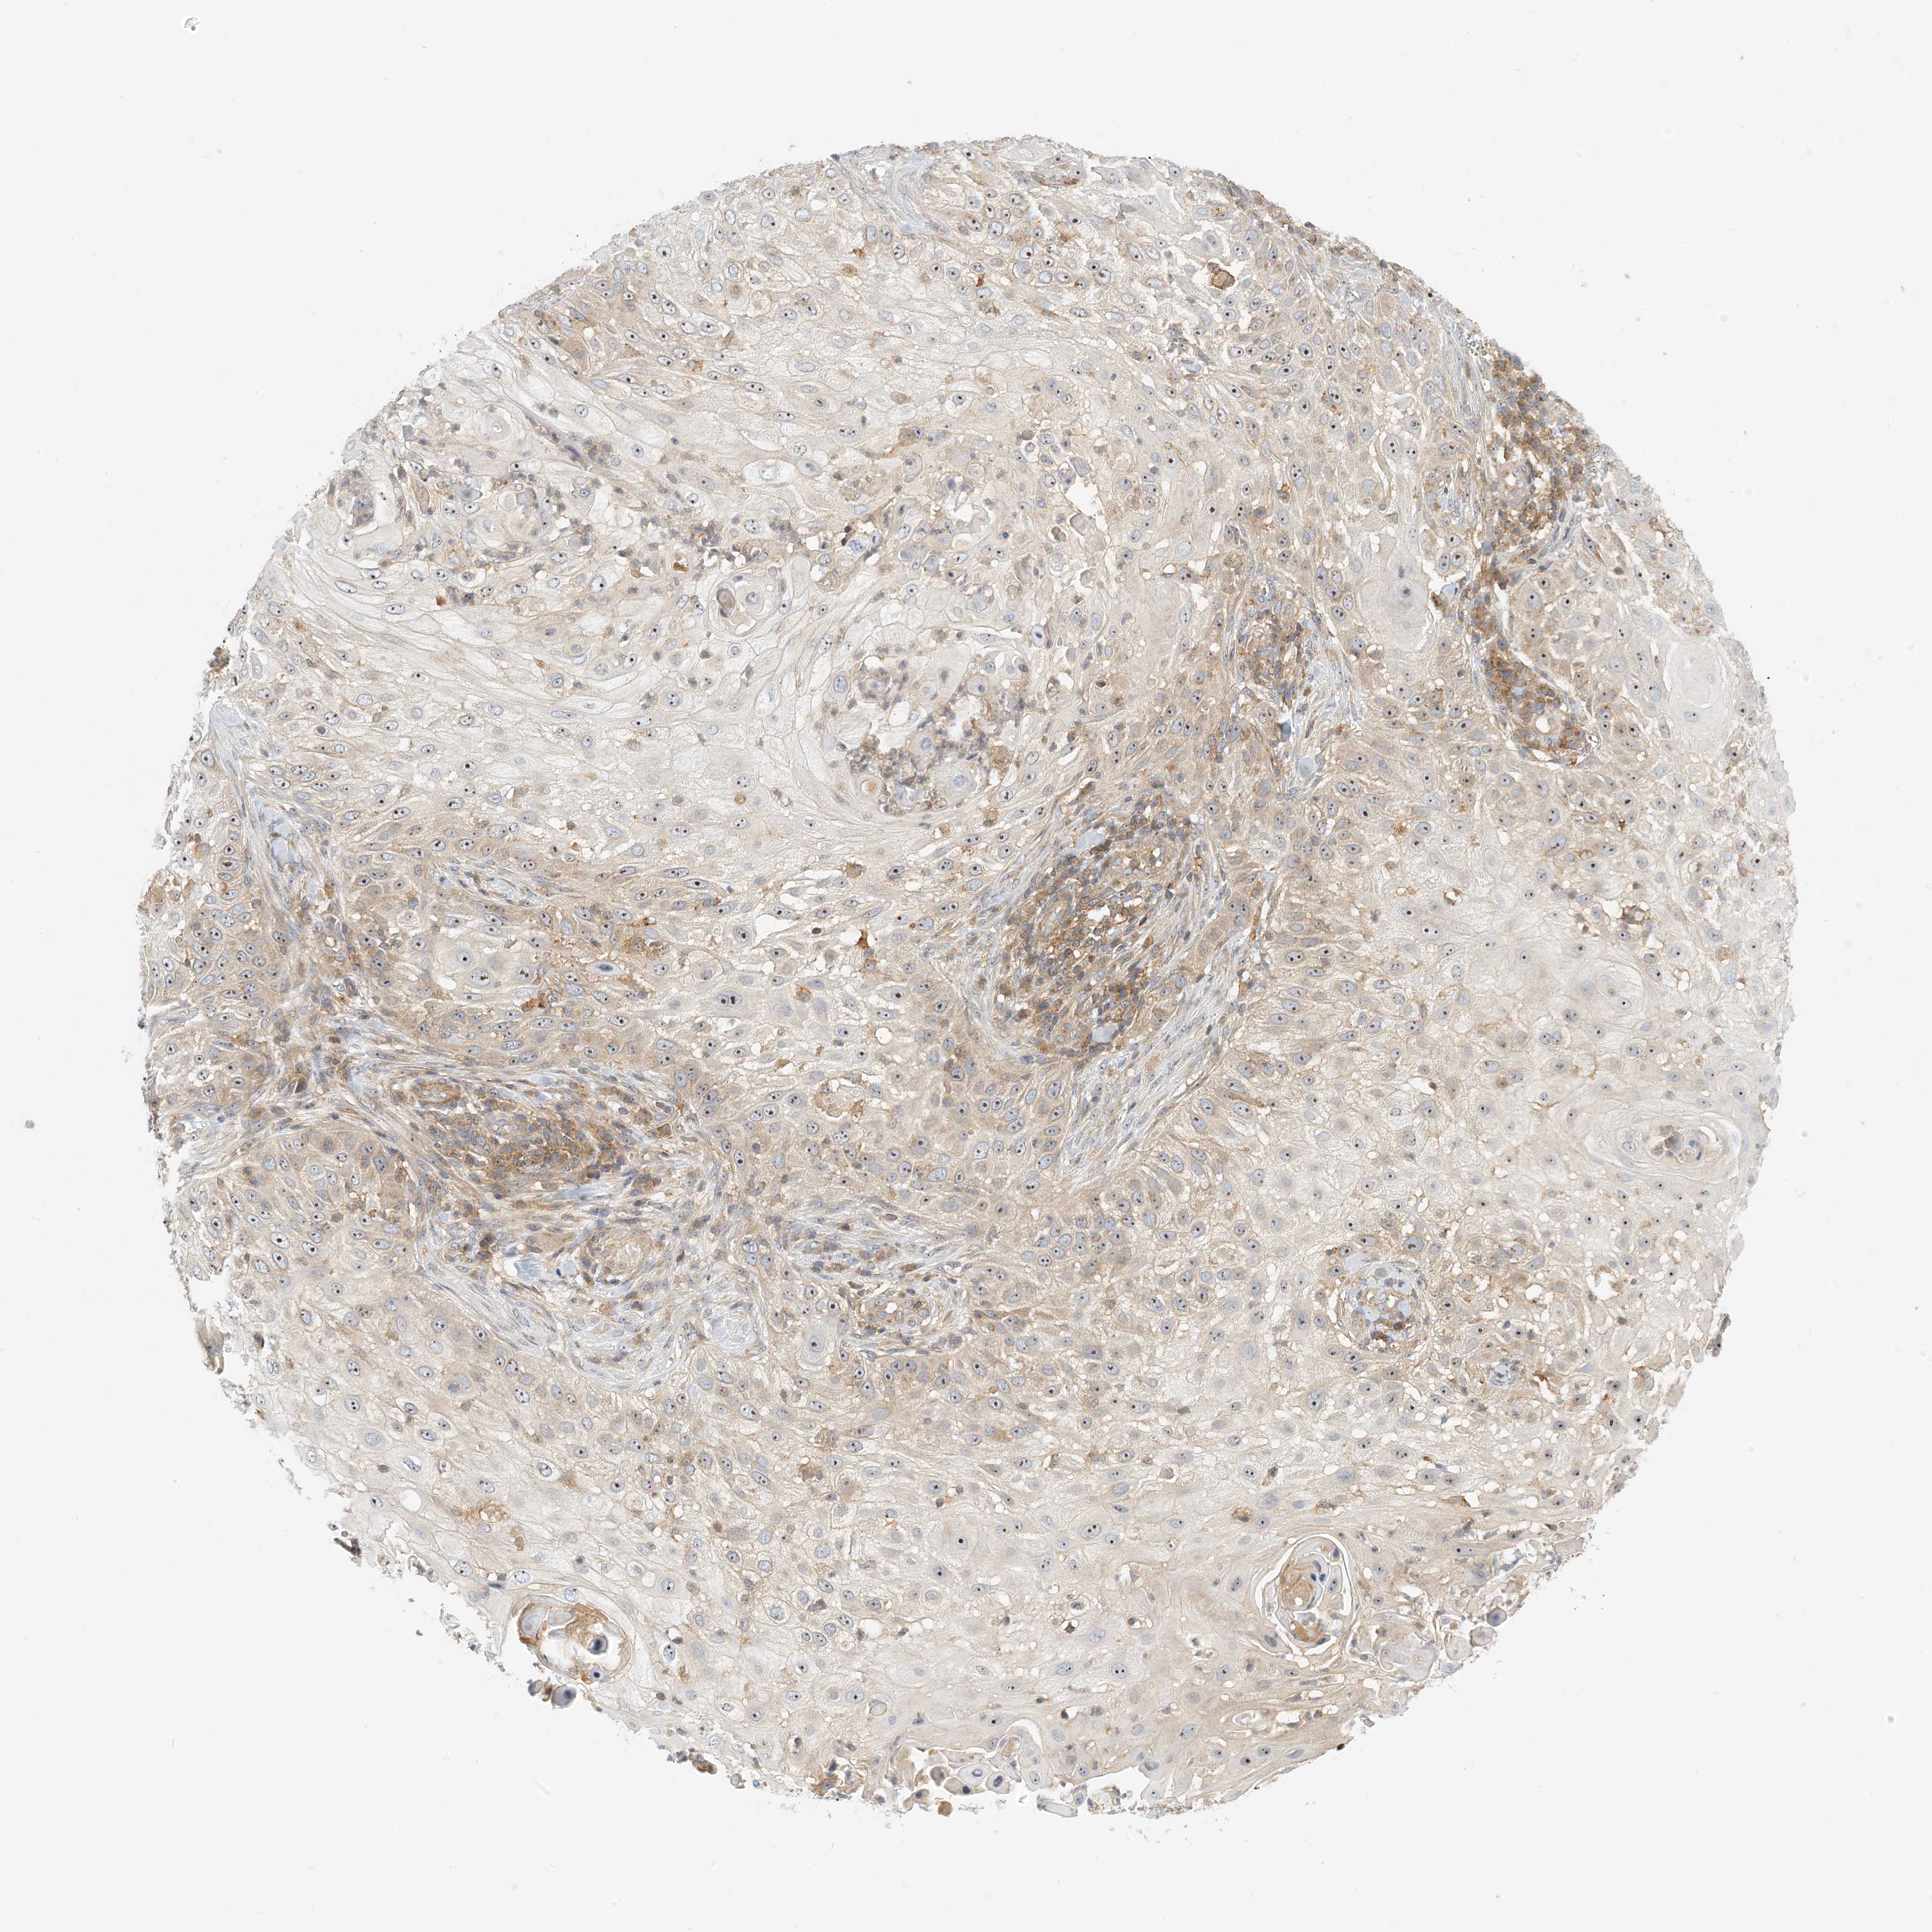

Basal cell and squamous cell cancer

SKIN CANCER - Protein expressioni

A mouse-over function shows sample information and annotation data. Click on an image to view it in a full screen mode. Samples can be filtered based on level of antibody staining by selecting one or several of the following categories: high, medium, low and not detected. The assay and annotation is described here.

Antibody stainingi

Antibody staining in the annotated cell types in the current human tissue is reported as not detected, low, medium, or high, based on conventional immunohistochemistry profiling in selected tissues. This score is based on the combination of the staining intensity and fraction of stained cells.

Each image is clickable and will lead to virtual microscopy that enables deeper exploration of all samples and also displays staining intensity scores, fraction scores and subcellular localization as well as patient and tissue information for each sample.

Antibody HPA035241

Staining

High

Medium

Low

Not detected

Intensity

Strong

Moderate

Weak

Negative

Quantity

>75%

75%-25%

<25%

None

Location

Nuclear

Cytoplasmic/membranous

Cytoplasmic/membranous,nuclear

Basal cell carcinoma